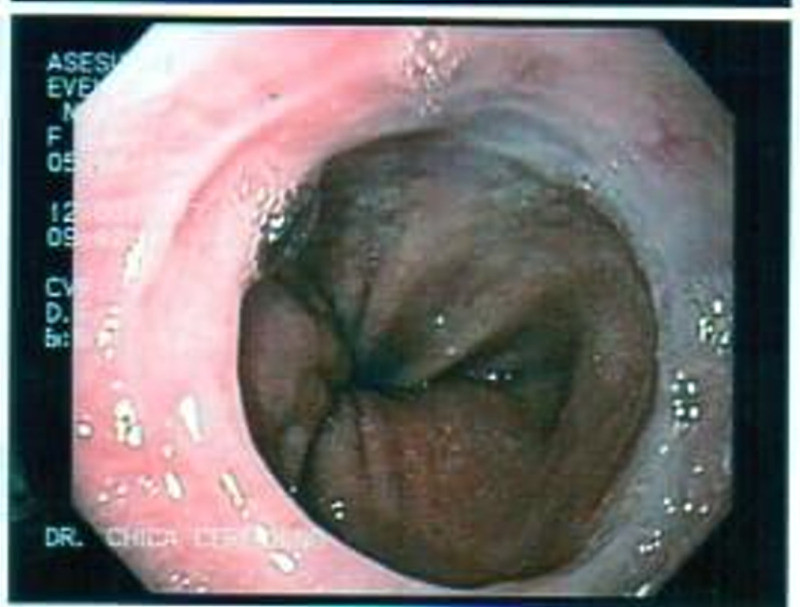

Paciente con enfermedad diverticular